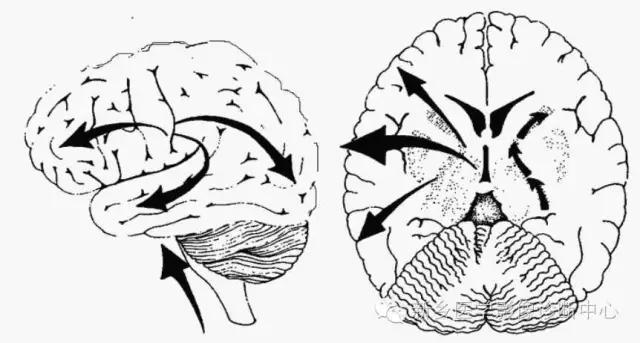

髓鞘化的进展遵循以下几个普遍原则:脑的后部,如枕部白质的髓鞘化优先于额颞叶白质,胼胝体压部先于膝部。

近侧通路先于远侧(如脑干先于幕上)

感觉(视觉和听觉)先于运动

中央白质先于外周白质

后部先于前部